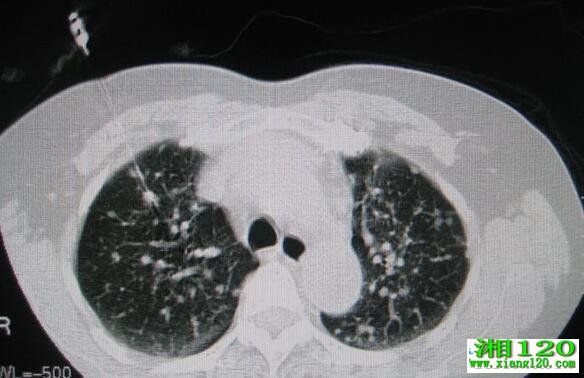

CT引导下经皮肺穿刺是一种对肺部疾病,特别是的一种中药诊断方式。主要的过程就是通过CT扫描帮助定位病变位置,然后通过细针穿刺或者活检枪对着病灶位置进入穿刺吸取出组织进行活检,然后进行病理组织学检查获得病变组织性质。